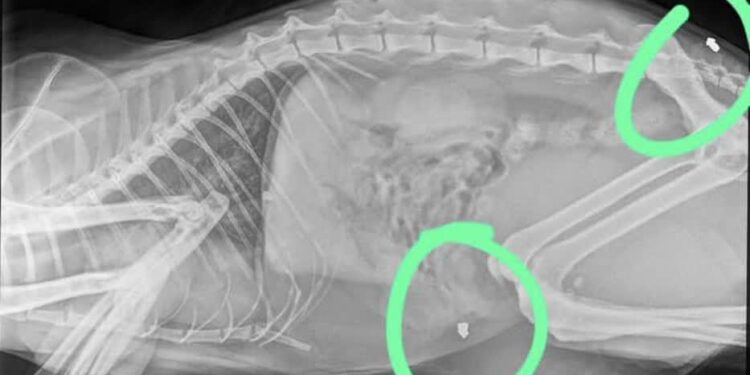

W weekend nasz kot został kilkukrotnie postrzelony z wiatrówki – grzybkowaty śrut jest w pobliżu kości krzyżowej i w otrzewnej. Poza tym ma jeszcze ranę na grzbiecie, najprawdopodobniej po nietrafionym strzale – relacjonuje w mediach społecznościowych pani Aleksandra:

Kot przeszedł już operację. Jeden fragment śrutu musiał pozostać w jego ciele, ponieważ usuwanie go niosło za sobą zbyt duże zagrożenie dla życia zwierzęcia. Całe zdarzenie zostało już zgłoszone na policję. – mówi pani Aleksandra: